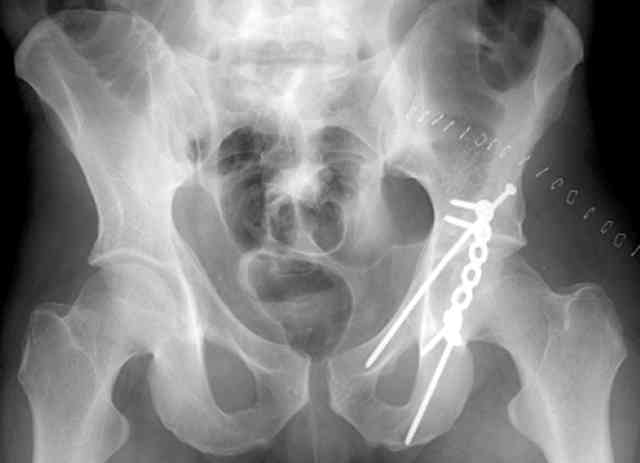

I'll include a few images of a similar injury in a similarly large male patient. This patient "showed up" in our ER c/o hip pain 2 months after being treated in the lateral position, without a quality reduction, without an anterior column transverse supporting implant, with an unbalanced plate applied too medially, with insufficient caudal segment fixation...it took over 8 hours and a 3+ l blood loss to debride the callus from front then

back, excise the HO, release his sciatic nerve, reduce the head-transverse-wall, and fix it...and now it's a staging procedure.